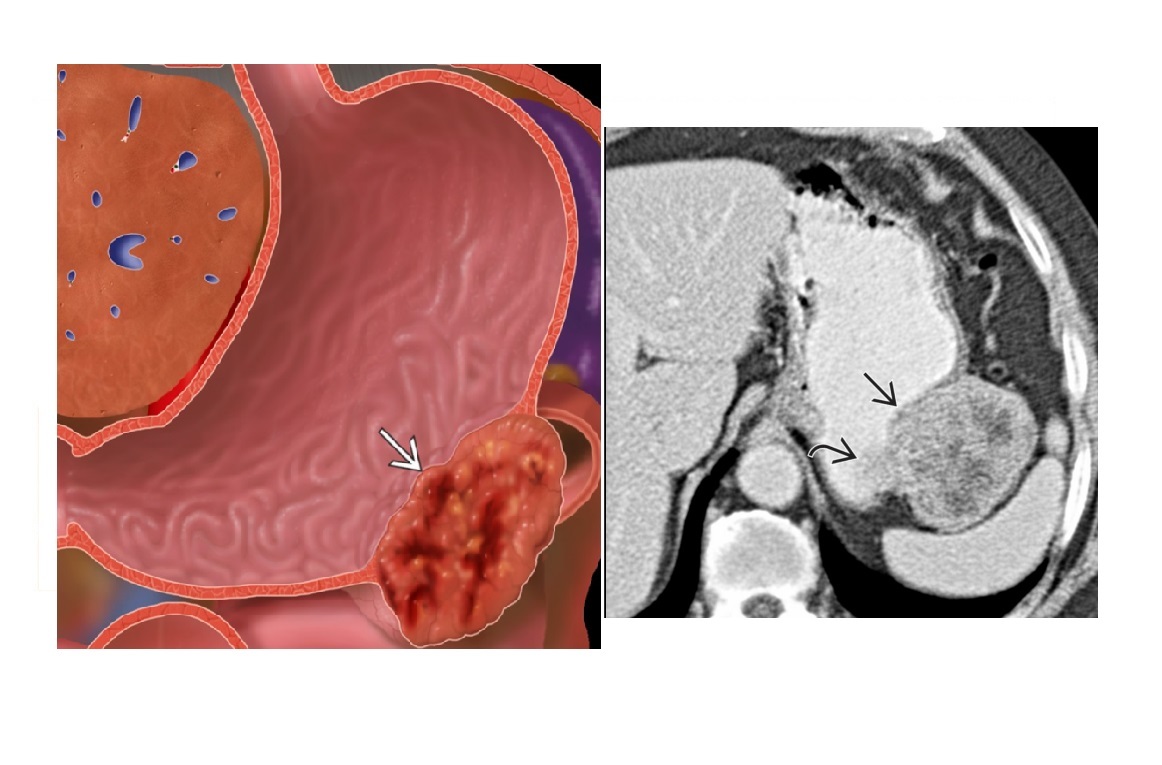

Features of GIST tumour?

A

Well-circumscribed.

Hypervascular

submucosal mass extending exophytically from GI tract

Stomach (70%)

**Heterogenous - Central necrosis is key **

Remember

- assocaited NF-1

- Carneys triad

- Pulmonary condromas, Exrtra-adrenal paragangliomas, GIST

How well did you know this?